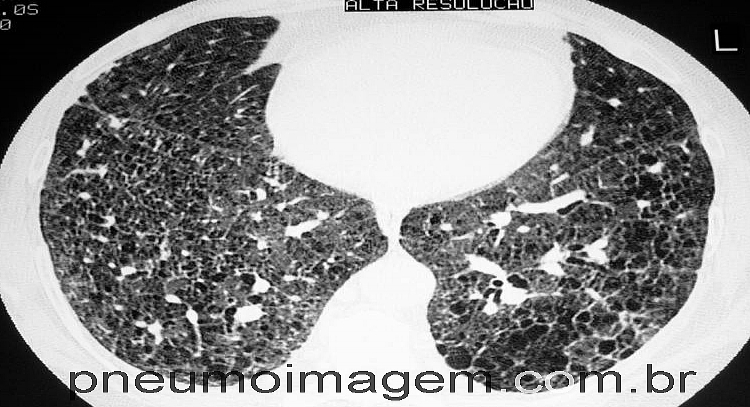

Um painel de especialistas das principais sociedades de especialistas em Pneumologia (ATS/ERS/JRS/ALAT) atualizou os critérios de diagnóstico para a Fibrose Pulmonar Idiopática (FPI). Padrões previamente definidos de pneumonia intersticial usual (PIU) foram refinados para os padrões de PIU, provável PIU, diagnóstico indeterminado e alternativo.

Para pacientes com doença pulmonar intersticial (DIP) recém-detectada que possuem um padrão de tomografia computadorizada de alta resolução de provável PIU, indeterminado ou um diagnóstico alternativo, recomendações condicionais foram feitas para a realização de LBA e biópsia pulmonar cirúrgica; por falta de evidências, nenhuma recomendação foi feita a favor ou contra a realização de biópsia pulmonar transbrônquica ou criobiopsia pulmonar.

Em contraste, para pacientes com DPI recentemente detectada que possuem um padrão de UIP à tomografia computadorizada de alta resolução, foram feitas fortes recomendações contra biópsia pulmonar cirúrgica, biópsia pulmonar transbrônquica e criobiopsia pulmonar, e uma recomendação condicional foi feita contra a realização de LBA. Recomendações adicionais incluíram uma recomendação condicional para discussão multidisciplinar e uma forte recomendação contra a medição de biomarcadores séricos com o único propósito de distinguir a FPI de outras DPIs.